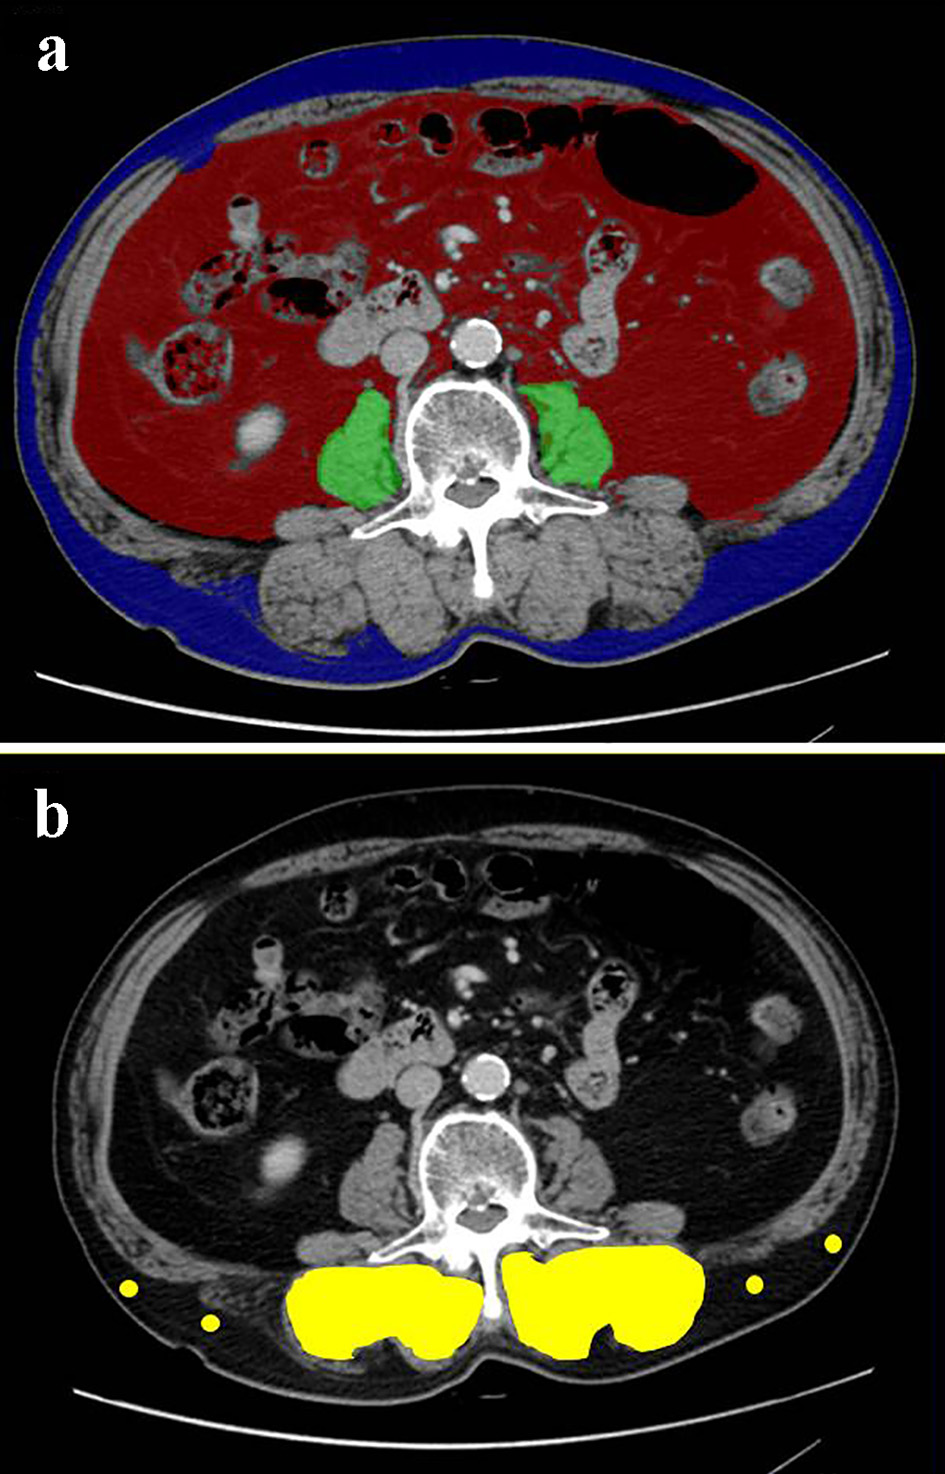

Using pretreatment and cross-sectional CT at the level of transverse process of lumbar vertebra L3, the skeletal muscle and adipose tissue areas were investigated by SYNAPSE VINCENT software (Fujifilm Medical, Tokyo, Japan). Using the CT attenuation values, the bilateral psoas muscle area, subcutaneous and visceral adipose tissue areas were automatically identified (Fig. 1a). PMI (cm2/m2) was defined by normalizing psoas muscle area (cm2) for the square of the patient’s height (m2) [15]. VSR was calculated by dividing VFA by SFA [16]. The multifidus muscles area was estimated by manual tracing method (Fig. 1b). IMAC was calculated by dividing the mean CT attenuation value (HU) of the bilateral multifidus muscles by that (HU) of four points of subcutaneous fat away from major vessels [17]. Unlike the previous studies [17, 18], in which the mean CT value of four small circles on subcutaneous fat was used, we adopted the mean CT value of four points on subcutaneous fat, because even small circles could not be placed in some thin patients’ subcutaneous regions. Based on the previous studies, as Japanese sex-specific cut-offs for PMI, IMAC and VSR, we used PMI cut-offs of 6.36 cm2/m2 for men and 3.92 cm2/m2 for women [15], IMAC cut-offs of -0.358 for men and -0.229 for women [19] and VSR cut-offs of 1.33 in male and 0.93 in female [16]. Based on the Japanese criteria of obesity disease [20] and the cut-off value of obesity-related cardiovascular risk factor [21], we pre-defined VFA cut-off of 100 cm2, irrespective of gender, age and BMI.

![]() Click for large image | Figure 1. Cross-sectional CT images at the third lumber vertebra level of a 75-year-old male patient. (a) The areas of bilateral psoas muscles (green area), visceral (red) and subcutaneous (blue) adipose tissue area were identified. (b) The multifidus muscle (yellow area) was precisely traced. Four points (yellow dots) were placed on subcutaneous fat away from major vessels. CT: computed tomography. |